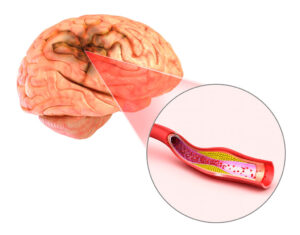

سکته مغزی ایسکمیک

در طی سکته ایسکمیک ، شریان های خونرسانی به مغز باریک می شوند یا مسدود می شوند.

این انسداد در اثر لخته شدن خون یا جریان خون ایجاد می شود که به شدت کاهش می یابد.

همچنین می تواند در اثر تکه های پلاک در اثر تجزیه تصلب شرایین و انسداد رگ خونی ایجاد شود.

مانند TIA ، سکته مغزی ایسکمیک در اثر انسداد شریان منجر به مغز ایجاد می شود.

این انسداد ممکن است یک لخته خون باشد ، یا ممکن است در اثر تصلب شرایین ایجاد شود.

با این شرایط ، پلاک (ماده ای چرب) روی دیواره های رگ خونی جمع می شود.

تکه ای از پلاک می تواند شکسته و در یک رگ قرار گیرد و جریان خون را مسدود کرده و باعث سکته مغزی ایسکمیک شود.